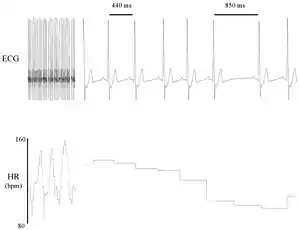

La variabilidad de la frecuencia cardíaca (VFC) es el fenómeno fisiológico de la variación en el intervalo de tiempo entre cada latido cardíaco. Se mide por la variación en el intervalo de latido a latido.

Otros términos utilizados incluyen: "variabilidad de la duración del ciclo", "variabilidad de RR" (donde R es un punto que corresponde al pico del complejo QRS de la onda de ECG ; y RR es el intervalo entre Rs sucesivas), y "variabilidad del período del corazón" .